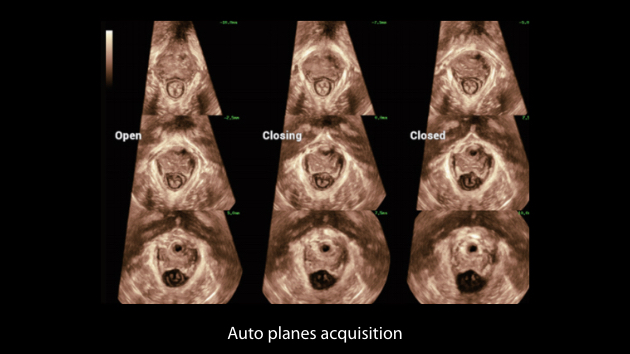

The Nuewa I9, dedicatedly designed for women and neonatal healthcare, providing an innovative experience from inside out.?These innovations are developed based on in-depth insights into complex clinical scenarios, providing accurate and timely answers as well as outstanding efficiency and remarkable user experience.

Clinical Images